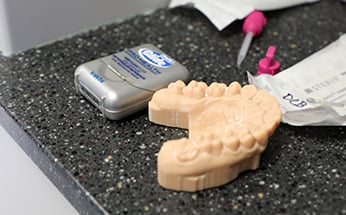

A model of Courtney's new smile was created using a state-of-the-art software program and a 3D printer.

The final product of Courtney’s crowns started with the dental school’s Trios scanner, which makes an oral impression by scanning teeth digitally, allowing them to be designed to the patient’s specifications. A model of her new smile was also created — the analog way — using a state-of-the-art software program and a 3D printer. Lastly, both the model and the digital imaging were sent to Peebles Prosthetics, which fabricated Courtney’s crowns using technology that further improves the design and quality of dental restorations.